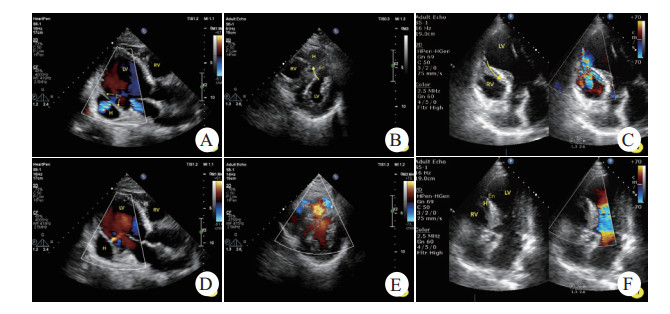

| A.左室后壁心肌内夹层血肿,内膜分离清晰可见,而心外膜完整,收缩期左室血流通过交通孔进入血肿内;B.舒张期血流再经交通孔返回左室;C.心尖肌层内血肿,内膜呈不规则断裂;D.左室血流涌入血肿并与右室交通,心肌交通路径非同水平;E.室间隔内匍匐状夹层瘤,左室面见断裂的心内膜,收缩期左室血流进入夹层瘤并再次破入右室;F.舒张期夹层瘤腔隙变小。LV.左室,RV.右室,H.夹层血肿/夹层瘤,En.心内膜 图 1 不同部位心肌夹层超声表现 |

1.1 病例1男,69岁,胸痛6 d,急诊查体发现心尖区Ⅲ/6级收缩期杂音,心电图提示“下壁、后壁导联ST段上抬”,当日床旁超声心动图提示“左室下后壁运动异常,心包腔少-中量积液”,未发现穿孔或夹层。收入CCU后杂音持续存在,次日申请超声会诊,提示“左室后壁中间段心肌夹层(夹层瘤大小1.8 cm×1.6 cm)”(见图 1-A, B),同日左心声学造影证实上述诊断。临床给予药物治疗。住院第13天复查床边超声发现夹层瘤较前增大(3.3 cm×2.8 cm);第24天左心声学造影发现夹层瘤处心外膜断裂,假性室壁瘤形成,心包积液增多。会诊无外科手术指征,介入亦对预后改善不详,继续以内科保守治疗为宜。30 d病情好转出院。6个月后门诊复查超声提示“左室下后壁心肌夹层假腔内血栓形成(4.4 cm×3.4 cm)”。

男,69岁,胸痛7 d,急诊查体发现胸骨左缘第4~5肋间4/6级连续性杂音,心电图提示“V1~4导联ST段抬高”,床边超声心动图提示“前间隔、左室前壁运动异常,左室心尖夹层瘤(2.5 cm×1.4 cm)形成并室间隔穿孔(非夹层水平)”(见图 1-C, D),临床治疗上给予药物治疗为主。1周后全麻下行室间隔封堵术,封堵未成功,术后患者血压进行性下降,一周后出现心源性休克,抢救无效死亡。

1.3 病例3男,70岁,胸痛2 d,急诊查体发现胸骨左缘第2肋间3~4级性质粗糙的收缩期杂音,心电图提示“前间壁相关导联ST段升高”,床旁超声心动图提示“前间隔、左室前壁运动异常并心尖部室壁瘤形成,室间隔穿孔并夹层,心包腔少量积液”(见图 1-E, F)。该患者放弃治疗。